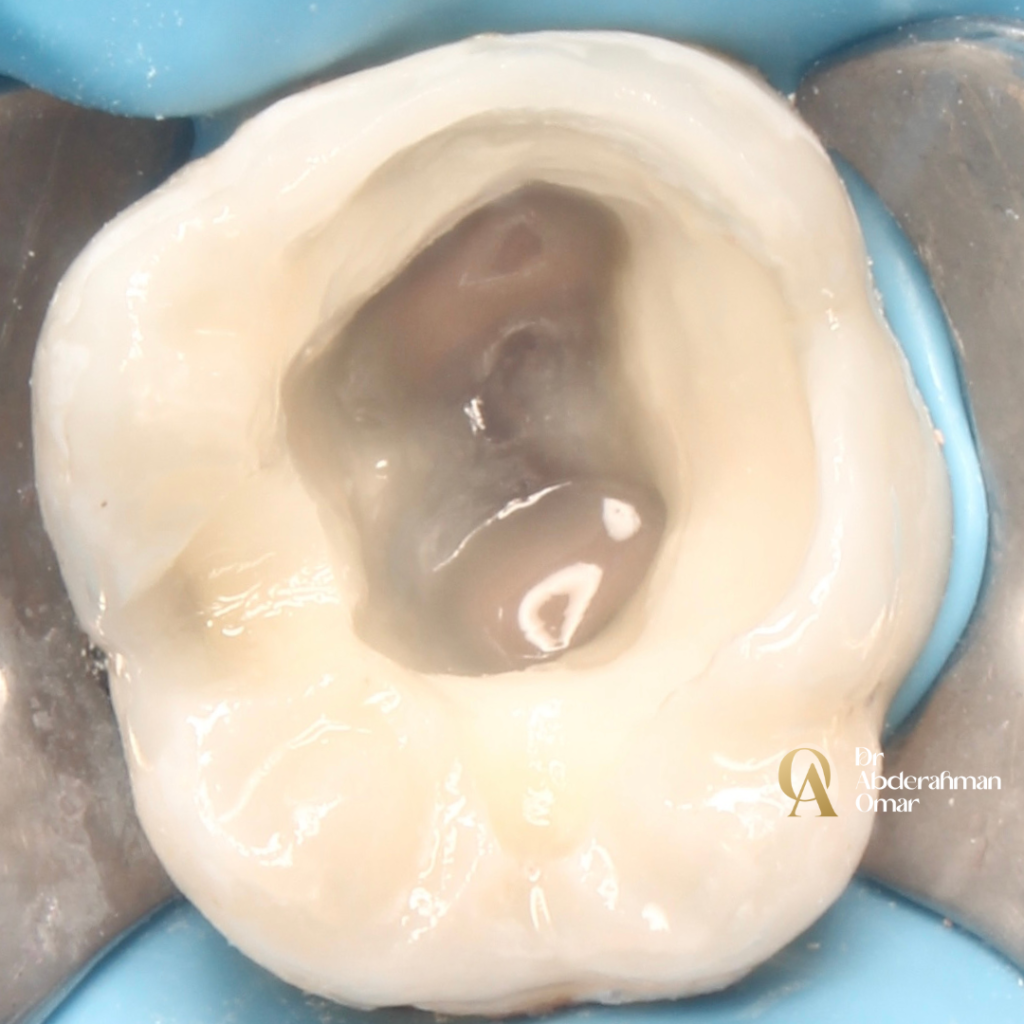

Upon access cavity preparation, careful exploration under magnification confirmed an atypical and complex canal anatomy: 5 distinct canals — 3 mesial canals (MB, MM, ML) and a Type III distal canal configuration (1 orifice dividing into 2 canals).

• Conservative access cavity preparation

• Identification of all canals under magnification